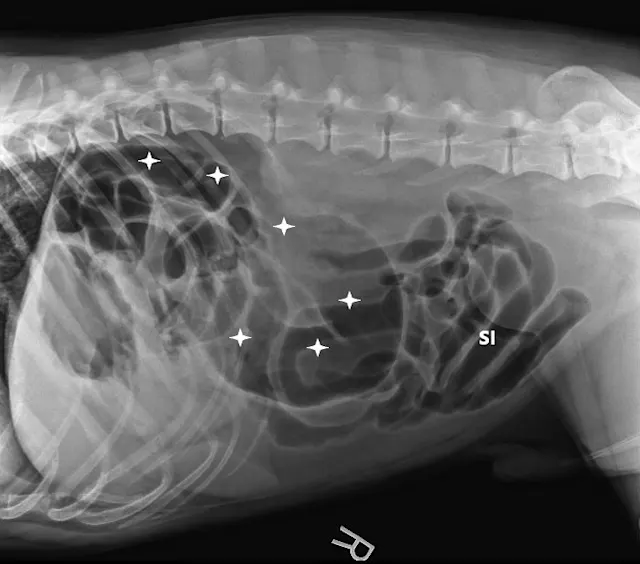

FIGURE 1A

Right lateral (A), left lateral (B), and ventrodorsal (C) abdominal radiographs demonstrating marked dilation of a single bowel loop with gas and amorphous material in the right cranial abdomen, suspected to be the colon (arrows). Caudal displacement of the small intestines (SI) can also be seen. The descending colon (Co) is poorly visualized.

Three-view abdominal radiographs revealed a single bowel loop markedly dilated with gas and amorphous material in the cranial abdomen thought to represent the colon due to its unusual position (ie, could not be tracked from caudal to cranial aspect on lateral radiograph; Figure 1). The small intestines were displaced caudally with no evidence of ileus (ie, gas filled but normal and uniform in diameter), and the descending colon was not fully visualized.